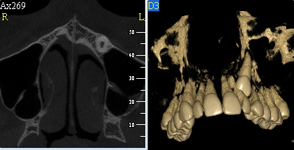

Pomocí tohoto přístroje je možné zjisti skutečnou situaci v čelistních kostech pacienta tedy množství kosti - můžeme změřit skutečnou šířku i výšku kosti, i kvalitu kosti (hustotu) v místě uvažované implantace. 3D (tříprostorové) zobrazení umožňuje

zvýšit prostorovou představu operatéra ještě před vlastní operací a zároveň pacientovi lépe objasnit a ukázat oblast plánovaného zavedení implantátu.

Pacient „neumí číst“ RTG snímky, ale díky 3D zobrazení vidí „svoji skutečnou čelist“ – např. jak je nízká či úzká, vidí průběh nervu nebo velikost čelistní dutiny, což mu umožní i pochopení nutnosti v některých případech provést pomocné zákroky

ještě před vlastním zavedením implantátu (více - Augmentace - kostní štěp, sinus lift, kostní granulát...).

Lékař si vytvoří všechny typy zobrazení potřebných pro naplánování – tedy 2D snímky (panoramatický), příčné řezy i 3D model.

Vidí zde i důležité anatomické útvary – čelistní dutinu, průběh nervu atd. Po proměření množství kosti – šířky i výšky vybere z databáze vhodný typ implantátu a umístí ho do požadované lokality.

Ihned vidí jeho pozici ve všech 3 rovinách a na všech snímcích i 3D modelu. Může upravovat podle potřeby jeho pozici, sklon atd.